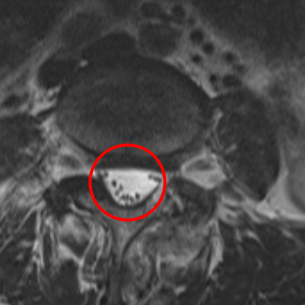

治療後

手術から1か月後、腰椎MRIを確認したところ、神経の圧迫を解消していることを確認しました。また左足の痛みと痺れは良くなったとのことだったのですが、お尻の右側に少し重みがあるとのことでした。この感覚は、神経損傷による後遺症と判断し、右L5にPRPを注入。術後3ヶ月目の検診時には、腰痛が10から0に、右下肢の痛みが10から2に、右下肢の痺れが10から1に。痛み止め薬を飲まなくても大丈夫なほどの改善効果が見られたため、さらに効果を高めようと、追加でPRPを注入しました。